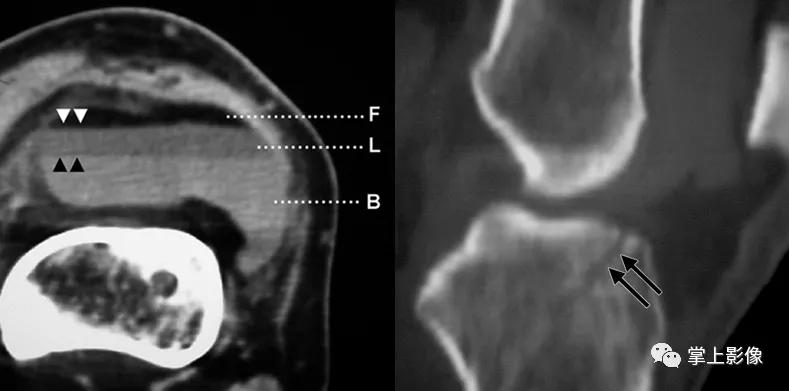

图1 、2为同一患者胫骨平台骨折合并积脂血症不同界面的 CT 表现,液平上方为脂肪,下方为关节内出血,可见单液-液平面征。图 3 为髌上囊积脂血征,胫骨平台骨折合并腓骨小头骨折。图 4 为 1 例隐匿性骨折患者,男,48 岁,车祸外伤,左膝关节活动受限,普通 X 线检查提示髌上囊内密度升高,常规平扫见脂液平面,经薄层重建充分显示左髌骨外侧缘撕脱骨折

- 对 CT 扫描的原始数据行薄层重建和多平面重组后可判断隐匿性骨折及微小骨折